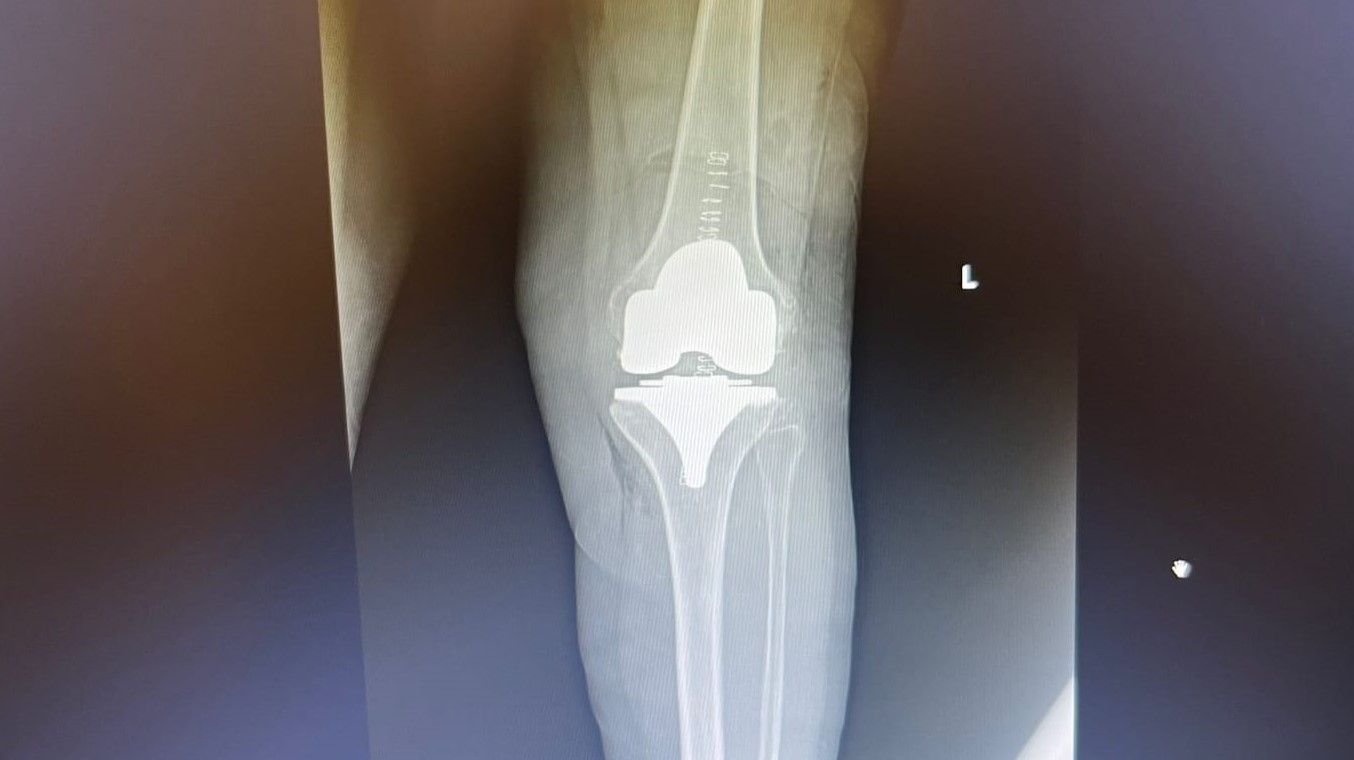

Con gli interventi di chirurgia protesica del ginocchio, ripristina la funzionalità e la mobilità dell’articolazione, sostituendo le superfici di scorrimento danneggiate e sagomando l’osso in modo da poter inserire la protesi. La scelta dell’impianto varia in base al paziente, in considerazione di parametri quali l’età, il grado di artrosi, la qualità dell’osso e la tenuta dei legamenti.

Quando l’artrosi interessa solo il comparto femoro-tibiale, si può utilizzare una protesi parziale o monocompartimentale ma, se è tutto il ginocchio a essere compromesso, la protesi totale è il trattamento di scelta.

La protesi di ginocchio è costituita da una componente tibiale, una femorale, entrambe in lega di cromo-cobalto, ed un inserto in polietilene che aumenta la congruenza articolare e la stabilità dell’impianto protesico. In genere, le componenti protesiche si fissano all’osso con il cemento, oppure utilizzando degli impianti in tantalio, materiale che si osteointegra completamente entro 3 mesi, senza necessità di cementare.